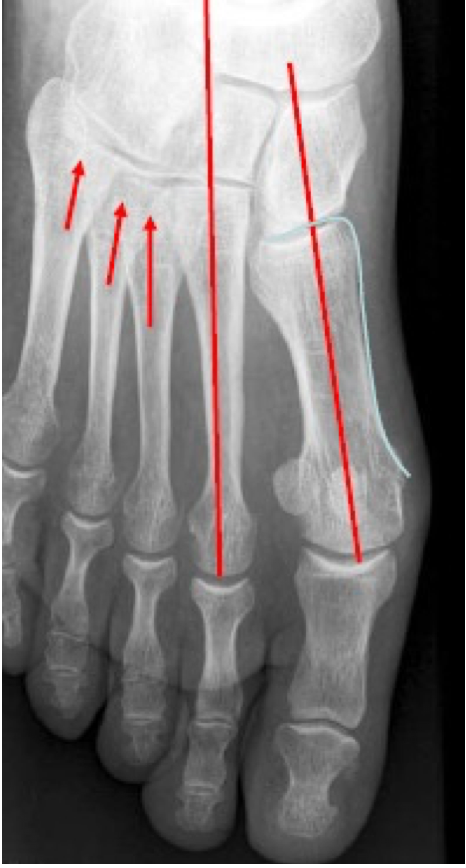

Normal anatomical alignment of the TMT joint should be assessed by evaluating the position of the tarsal bones in relation to the adjacent metatarsals Fig 11).

In the normal foot, the lateral border of the medial cuneiform is aligned with the lateral border of the base of the first metatarsal. In addition, a collinear relationship is present between the medial border of the base of the second metatarsal and the adjacent intermediate cuneiform. Similarly, the medial border of the base of the fourth metatarsal is aligned with the medial border of the cuboid, which can only be sufficiently assessed on the medial oblique radiographic projection (Fig. 12). Misalignment of 1 mm or more has been characterized as pathological. (27)

In the front view, the medial edges of M2-C2 (blue dotted line) and M3-C3 (green dotted line) must be aligned. The lateral edges of M1-C1 (red dotted line) should be aligned (Figure 13).

The gap between C1 and M2 should be less than 2 mm. The assessment of medial TMT joint line stability was described by Coss et al (28) using the abduction stress manoeuvre.